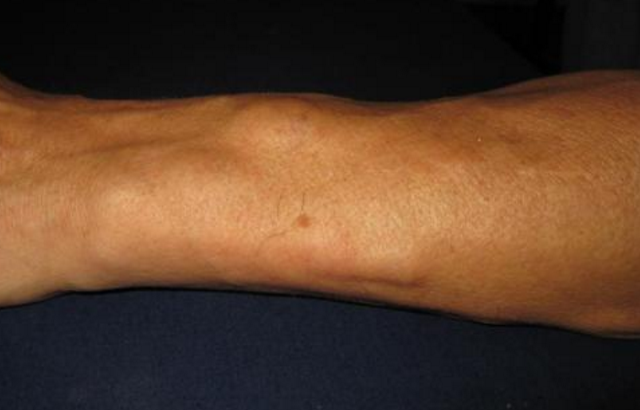

脂肪瘤圖片

脂肪瘤